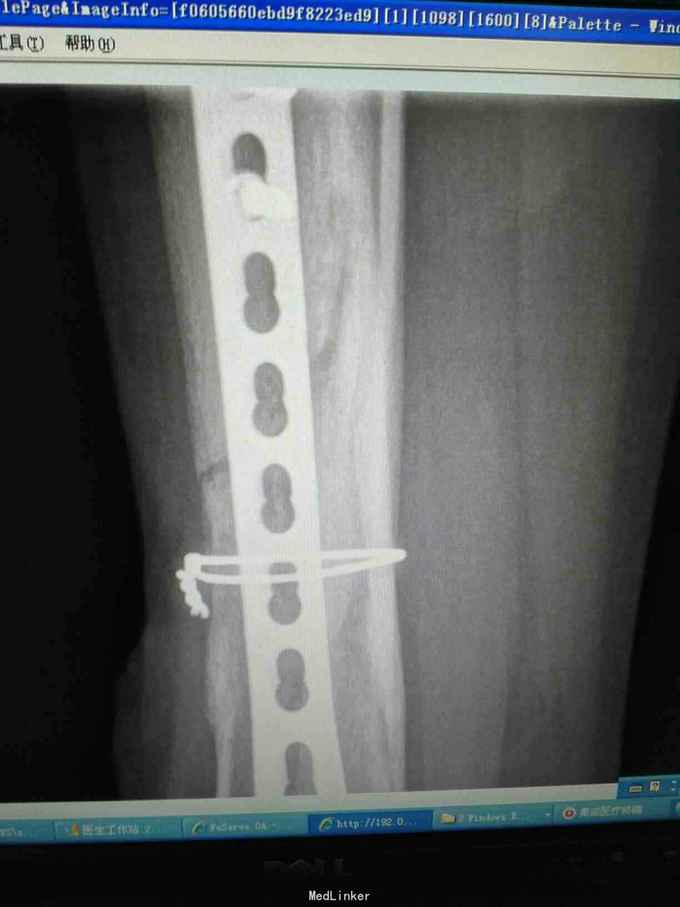

男性患者,因外伤后胫骨骨折行钢板内固定,术后因创面不愈合,于49天转我科,局部负压吸引,植皮封闭,约3月半出院,出院后3月因皮肤破溃钢板外露再次入院

一般情况好,X线提示部分骨痂生长,小腿内测中下段可见皮肤破溃,局部红肿,部分渗出,骨及钢板外露

入院请骨科会诊并加强局部换药,创面清洁后接受骨科建议,术中拆除钢板并并小腿内侧双蒂皮瓣转移覆盖,术中皮瓣下放置负压引流管,术后2天拔除,术后7天术区情况好